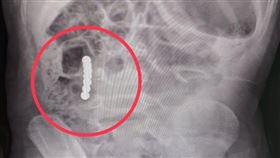

1歲嬰腹脹狂吐 肚見「10恐怖白點」穿破腸

一名媽媽某日抱著1歲多的男嬰衝進兒童急診室,表示孩子...

2歲童狂吐!照X光嚇:10恐怖白點

父母要隨時注意小孩的玩具!一名2歲男童在3天內瘋狂嘔...